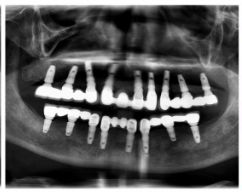

通過(guò)X光片可以看到,醫(yī)生雖然盡量設(shè)計(jì)連冠種植,但還是用了十七個(gè)植體,盡管已經(jīng)是多次調(diào)整后的精簡(jiǎn)方案,但手術(shù)時(shí)長(zhǎng)依然長(zhǎng)達(dá)一天。位老先生之前在另一家醫(yī)院咨詢時(shí),醫(yī)生給的方案是種二十二個(gè)植體,光是種植費(fèi)用就令人大呼“害怕”了。

種植修復(fù)后X光片

這一位老先生則選擇了All-on-4種植技術(shù),即拔即種,上下頜分別種植4個(gè)植體就完成了全口牙齒修復(fù),費(fèi)用降低了不少,而且創(chuàng)傷小,恢復(fù)快。